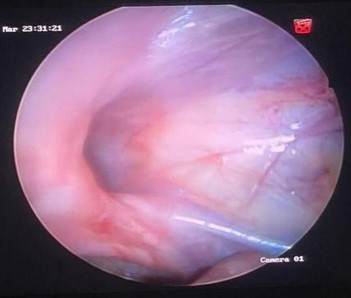

Figura 5. Retiro de aguja e introducción de material prolene 2.0

Nota: se retira la aguja dejando el hilo en cavidad, se introduce de igual forma material prolene 2.0 (2do hilo) en forma simple para localizar la lazada e introducir ese hilo en la lazada.